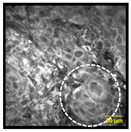

| Multinucleated Cells: Squamous cells that appear poly nuclear or have more than one nuclei per cell | ![]() | ![]() | 16% | 85% | 93% |